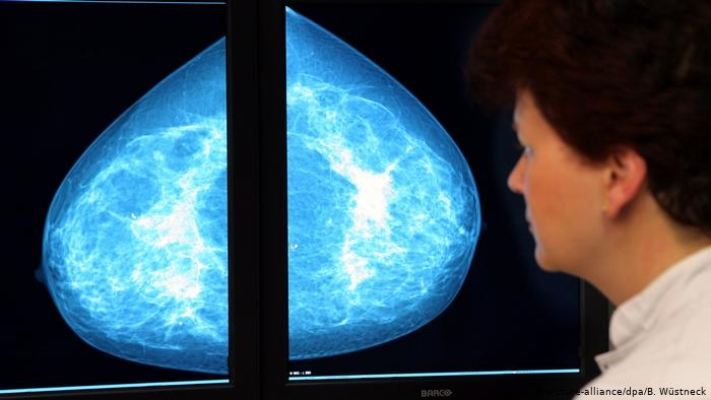

Bei der Früherkennung von Brustkrebs, Gebärmutterhalskrebs und Darmkrebs will die EU-Kommission erreichen, dass 90 Prozent der Bevölkerungsgruppen, die für ein Screening in Frage kommen, bis 2025 auch tatsächlich daran teilnehmen. Auch hier gibt es erhebliche Unterschiede in den Mitgliedstaaten. Während in Westeuropa die Programme voll entwickelt sind, gibt es in Bulgarien oder Griechenland keine systematischen Ansätze.